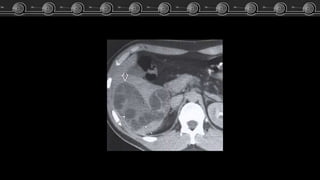

• Fase arterial: Captación

nodular periférica en fase

arterial, con captación lenta y

progresiva, centripeta e

isodensa respecto a los vasos.

• Fase venosa: Captación

progresiva, centripeta hasta el

relleno uniforme.

TC

Hemangiomas Cavernosos • Fase arterial:Captación nodular periférica en fase arterial, con captación lenta y progresiva, centripeta e isodensa respecto a los vasos. • Fase venosa: Captación progresiva, centripeta hasta el relleno uniforme. TC • Simple: Isodensa o hipointensa.